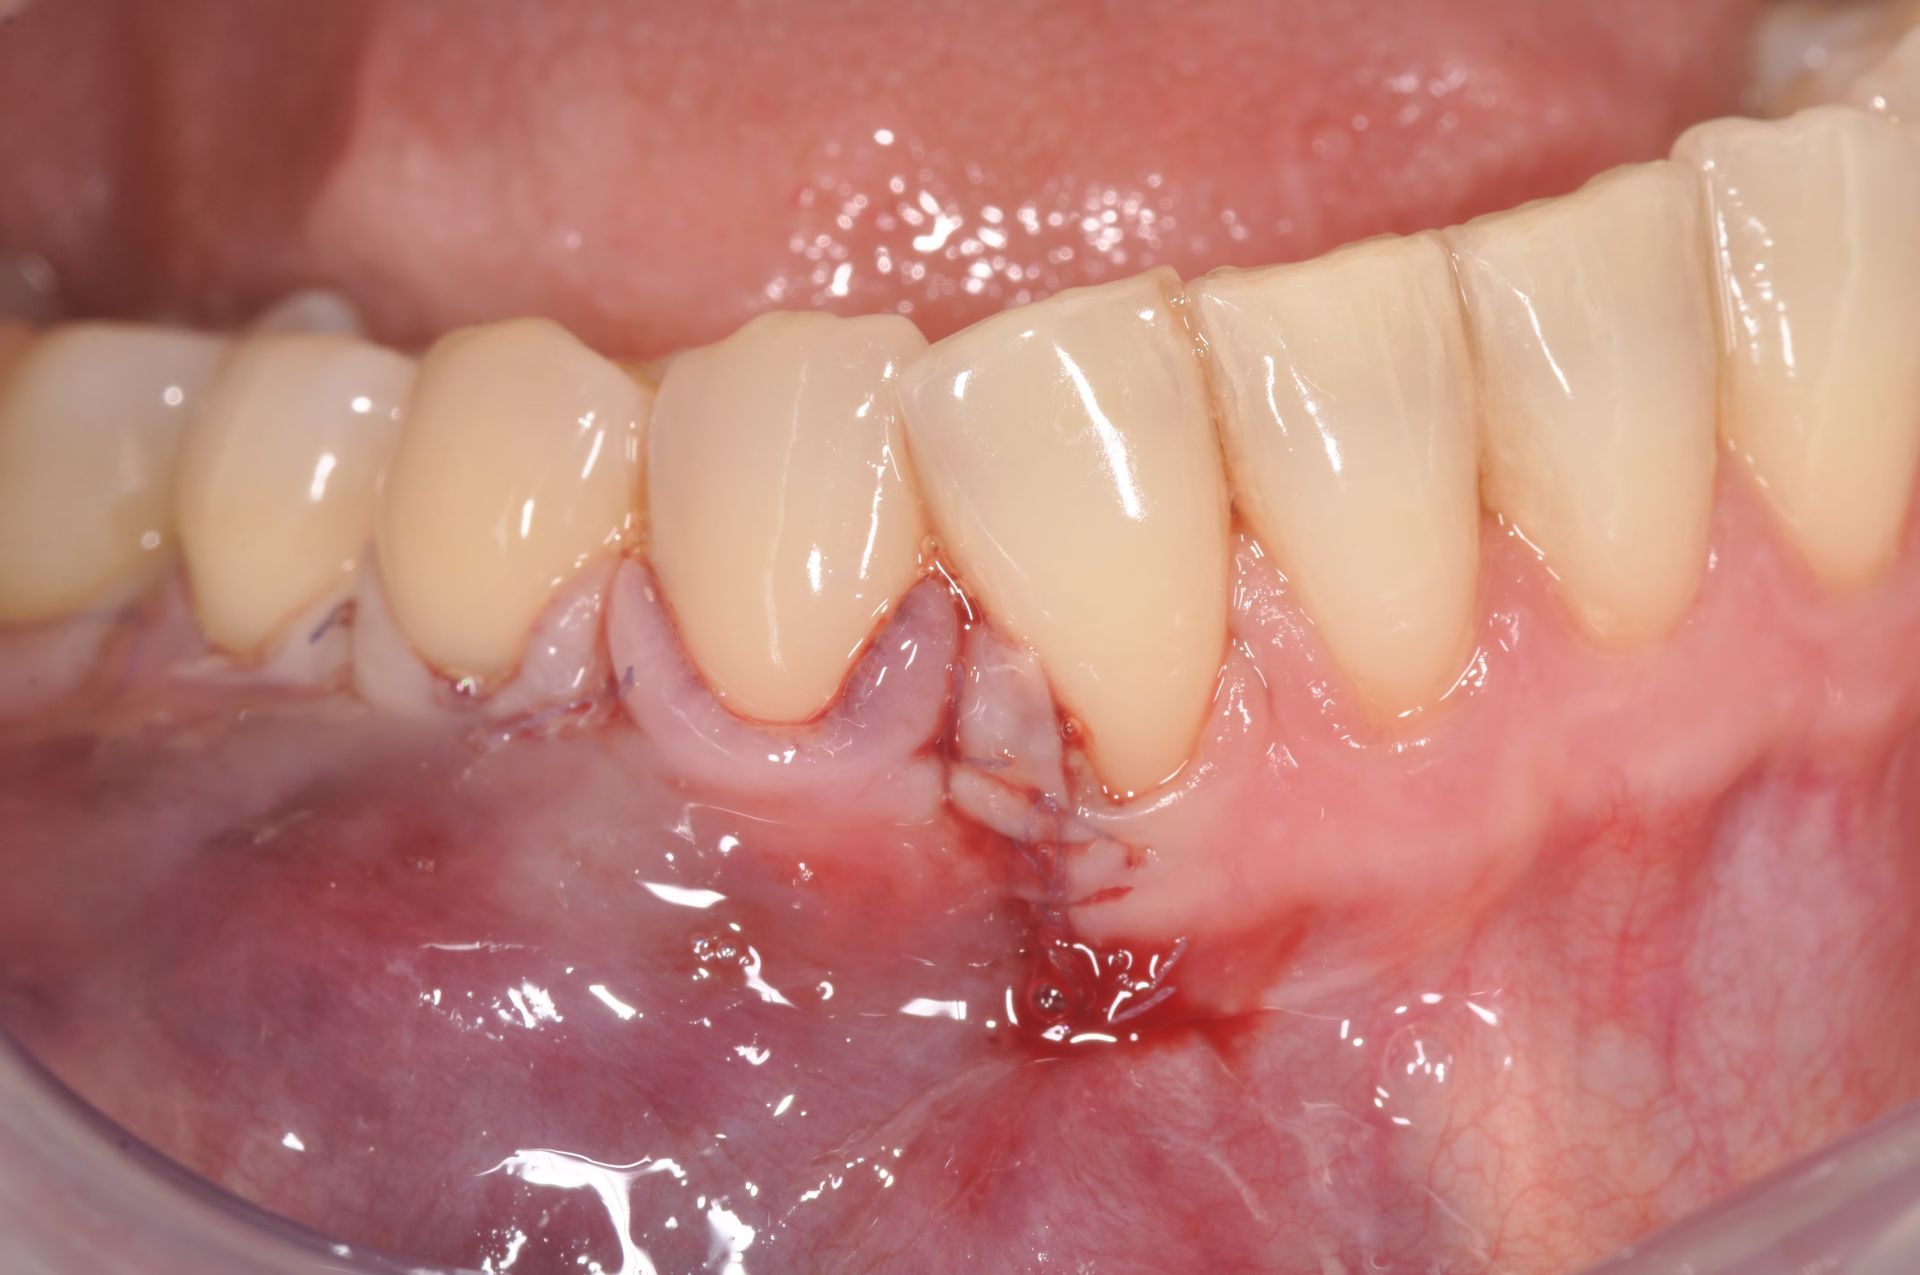

Chirurgia Mucogengivale

Trattamenti dedicati alla correzione di recessioni, difetti gengivali e alterazioni estetiche del sorriso. Sono procedure ad alta precisione, svolte da uno specialista di fama internazionale, per risultati naturali, armoniosi e stabili nel tempo.

La chirurgia muco gengivale include i trattamenti dedicati alla correzione di recessioni, difetti gengivali e alterazioni estetiche del sorriso. Richiedono una tecnica che funziona nelle mani di pochi, per questo il nostro centro si avvale di uno specialista di fama internazionale, per risultati naturali, che garantiscano il successo atteso e, soprattutto, siano stabili nel tempo.

Tutti gli interventi di chirurgia orale vengono eseguiti in una sala chirurgica dedicata, in presenza di un medico anestesista, con possibilità di ricorrere alla sedazione cosciente, una procedura anestesiologica sicura e controllata che permette al paziente di entrare in uno stato di profondo rilassamento, pur rimanendo sveglio e collaborante, riducendo ansia e stress e garantendo serenità e comfort al paziente durante tutta la procedura.